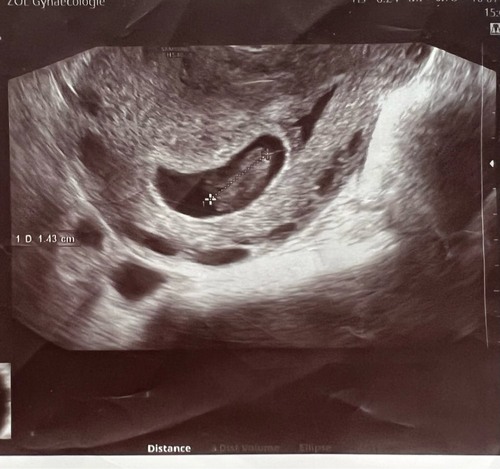

Wat verdrietig, veel sterkte! Zie ik dat er 10.1cm staat?

Toen ik 7 weken+2 was was de baby 10.9cm

10,9 mm bedoel je.

10cm is onmogelijk met 7 weken